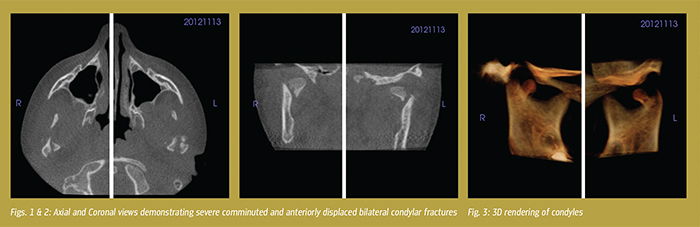

The patient was followed with low dose 3D imaging through a period of progressive mobilization and "guiding" elastic inter-maxillary fixation with physical therapy using Rocabado 6x6x6 protocol. The goal was to improve his range of motion, gain consolidation of the condylar fragments, and prevent ankylosis. Over the intervening months, follow up was completed to monitor consolidation of the condylar segment, the development of new articulation and growth of the condyles to a more normalized position (Figs. 4-5).